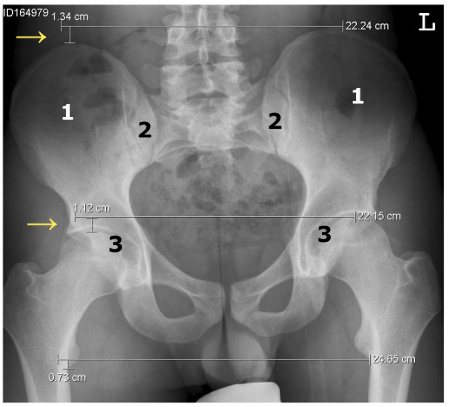

Ausgangspunkt vieler Beschwerden im Bewegungsapparat ist das Becken. Es besteht aus den beiden Hüftbeinen (siehe "1" auf dem Röntgenbild unten), die über das Iliosakralgelenk (ISG, siehe "2") mit dem Kreuzbein verbunden sind. Bei der Beckenverwringung sind die beiden Hüftbeine gegeneinander verdreht. Dies führt zu einer veränderten Lage der beiden Hüftgelenkspfannen (siehe "3"), weshalb ein Bein kürzer als das andere erscheint (siehe "→"). Man spricht von einer funktionellen Beinlängendifferenz. Das ist ein scheinbarer Unterschied der Beinlängen infolge einer Fehlstellung des Beckens und der Wirbelsäule - im Gegensatz zu einer anatomischen Beinlängendifferenz, bei der die Beine tatsächlich verschieden lang sind.